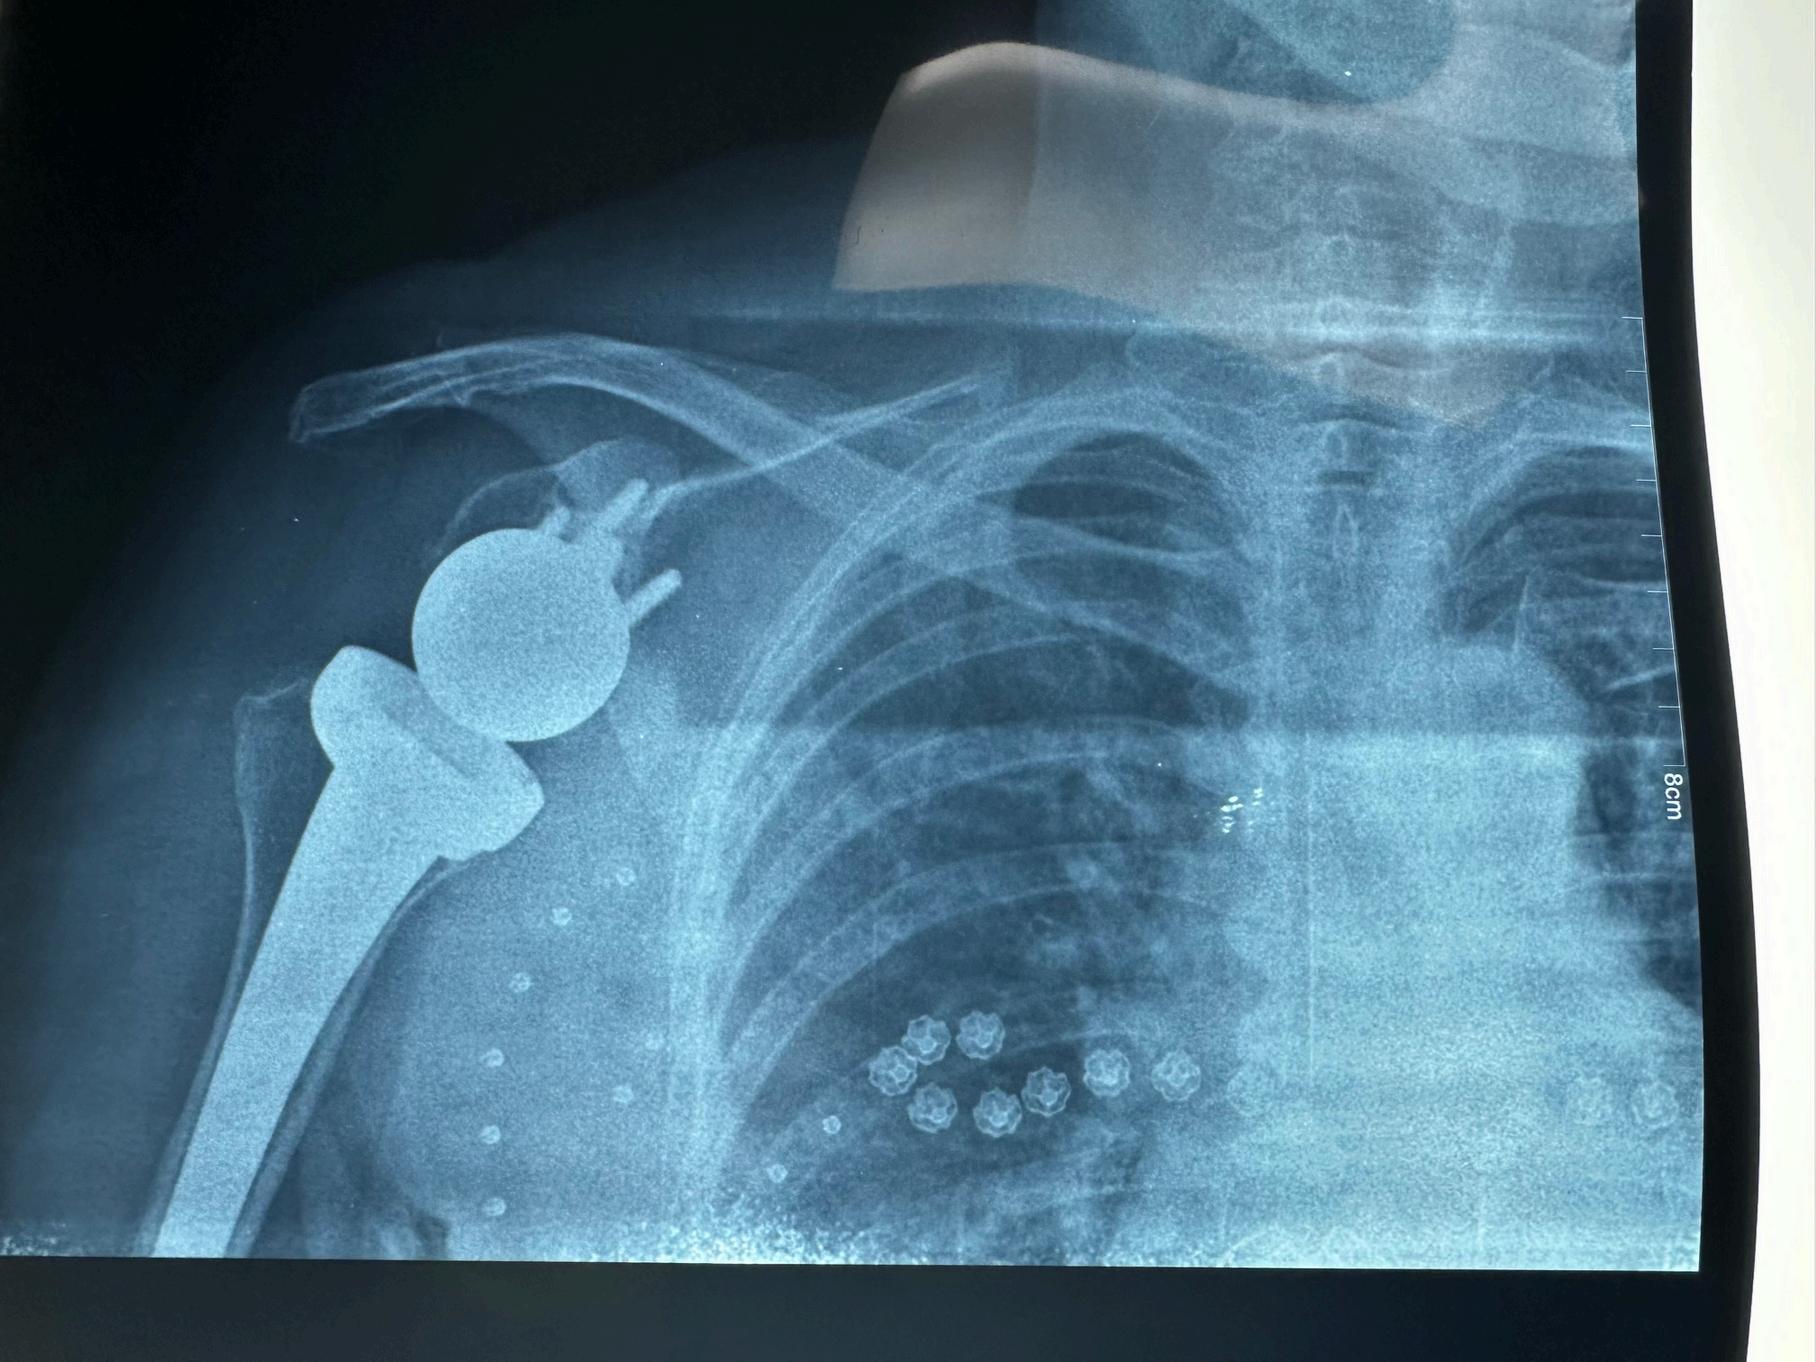

Innovation was the driving force behind our department's success. This year, we unveiled several initiatives aimed at integrating the latest technological advancements into clinical practice One of these innovations includes our own prosthetic lab to support our rapidly growing boneanchored limb program This collaborative endeavor is supporting our patients with state-of-the-art prosthetics and together we will continue to find even more novel solutions.